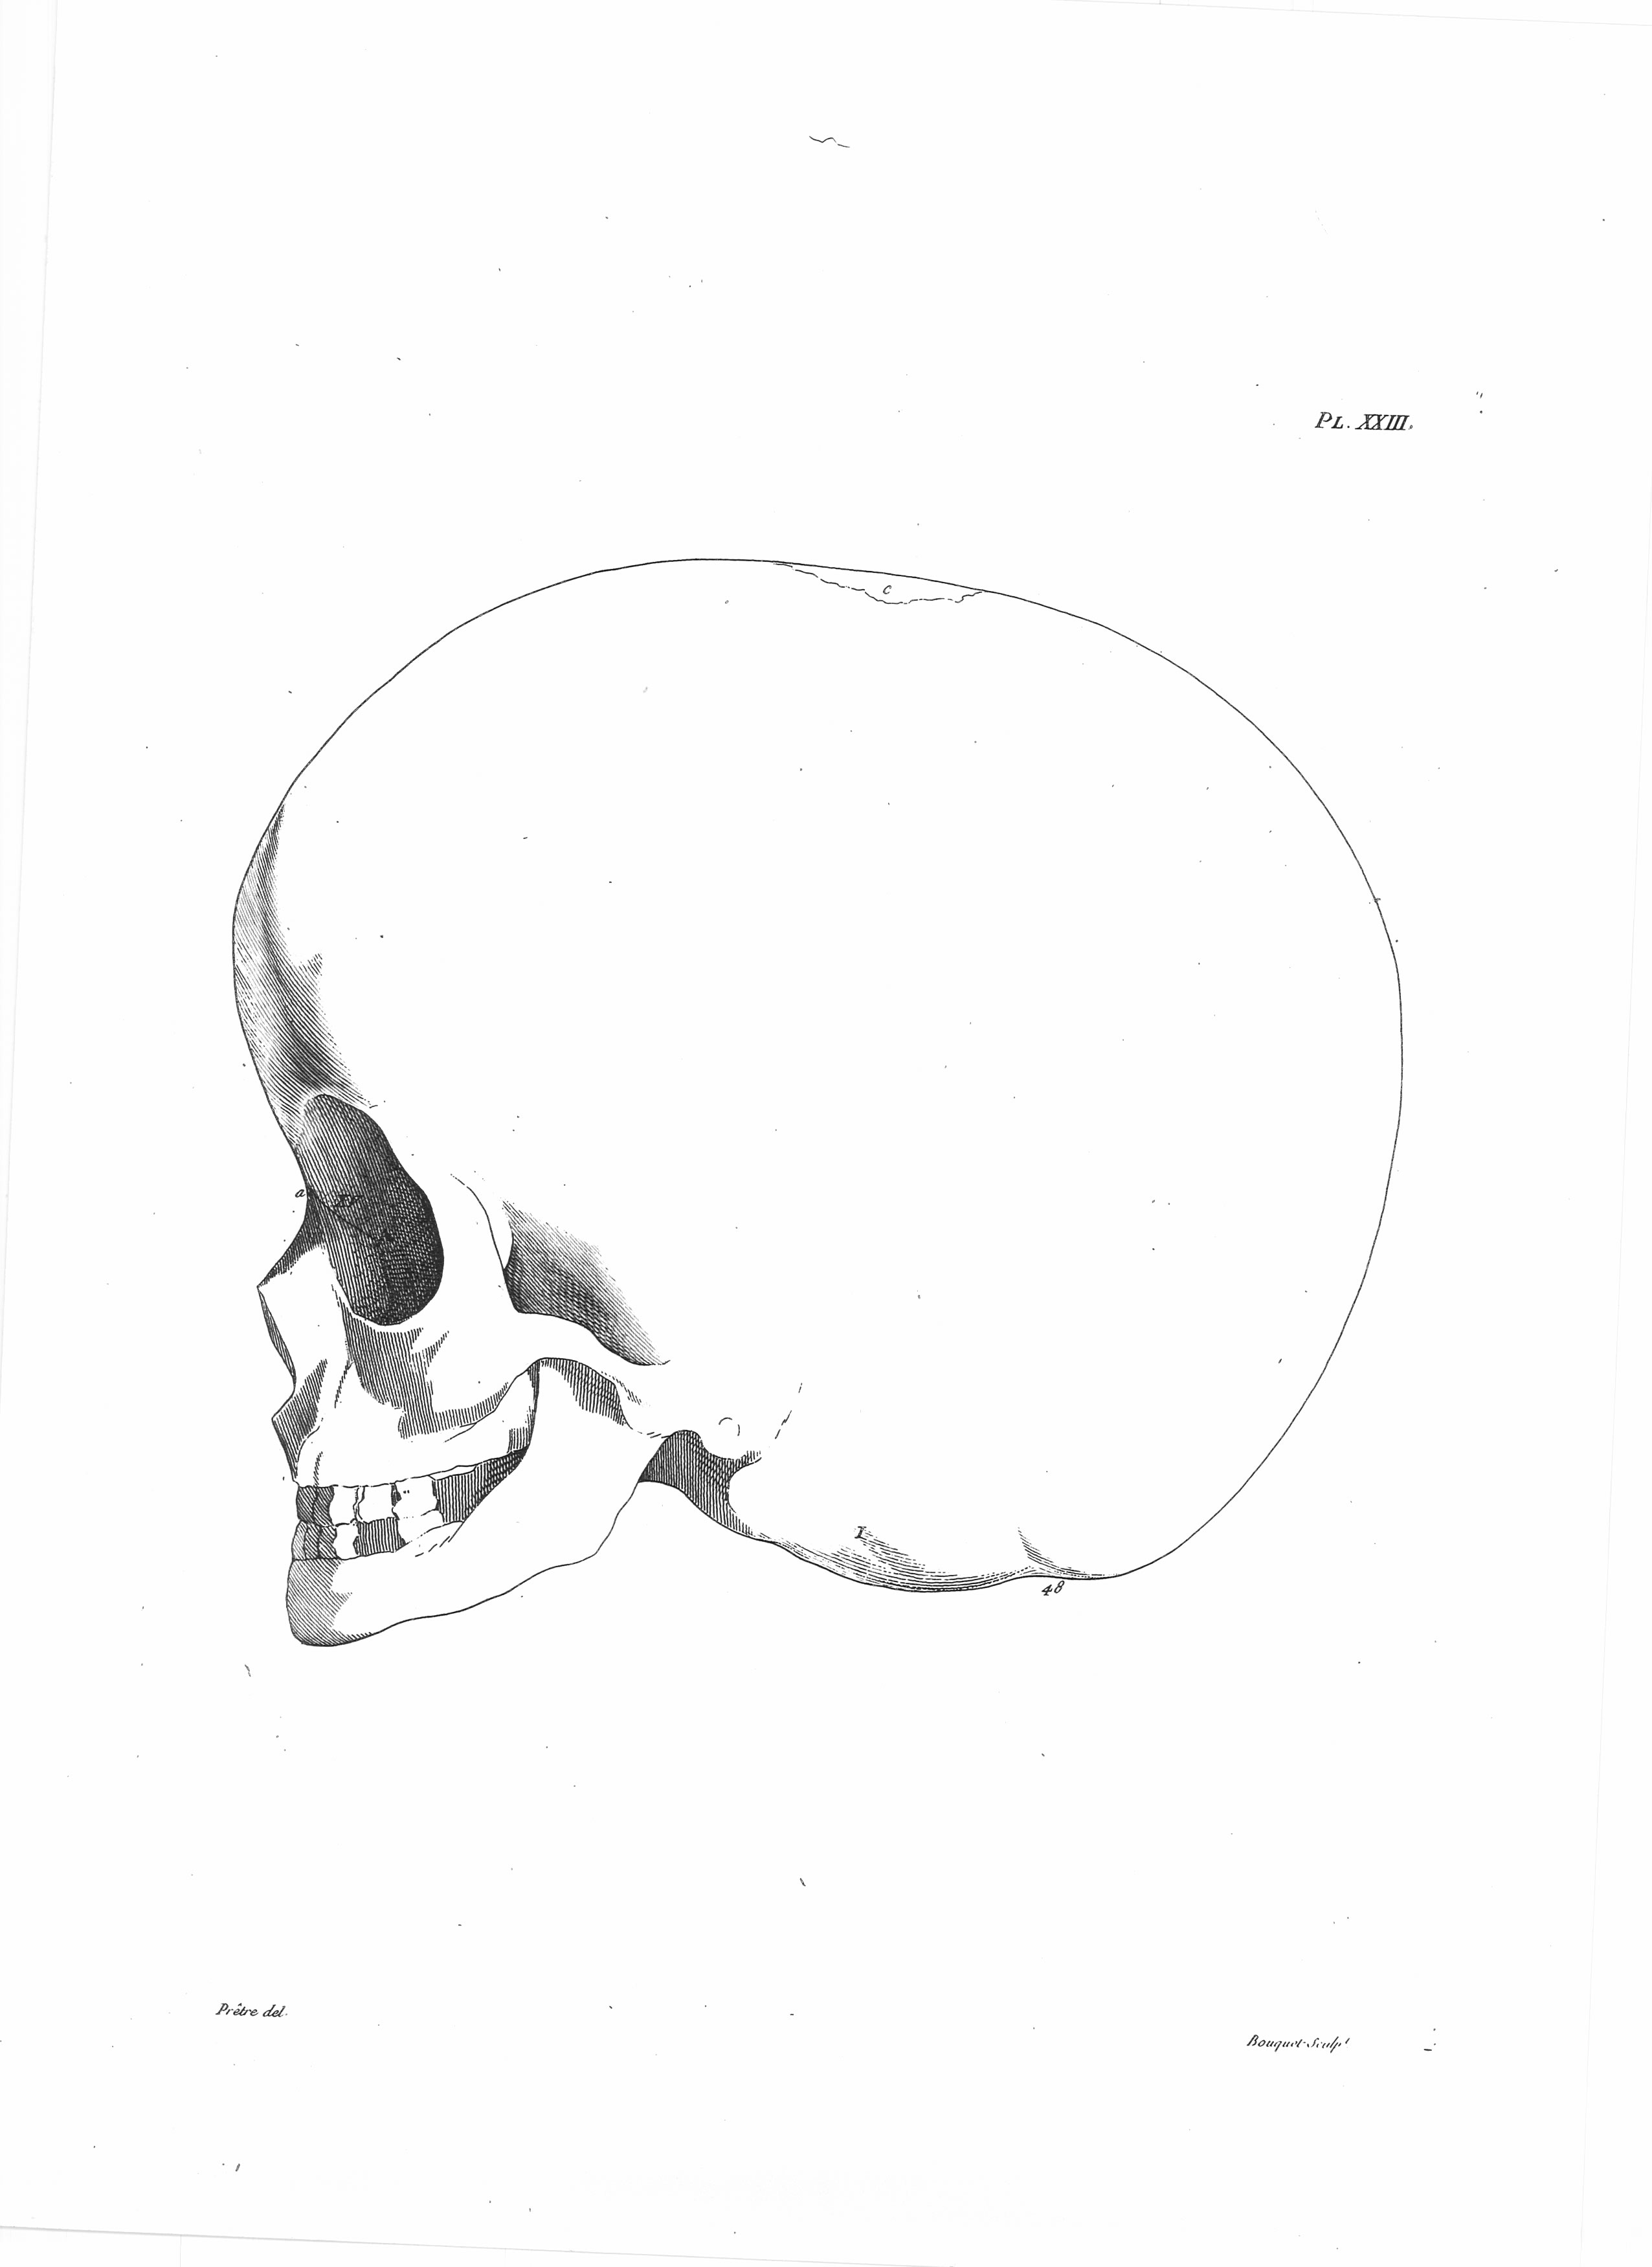

Gall, F. J. (1818). Anatomie et physiologie du système nerveux en général, et du cerveau en particulier, Avec des observations sur la possibilité de reconnoître plusieurs dispositions intellectuelles et morales de l´homme et des animaux, par la configuration de leurs têtes.

Librairie Grecque-Latine-Allemande, Vol. 3, I-XXXV u. 1-379 100 planches.